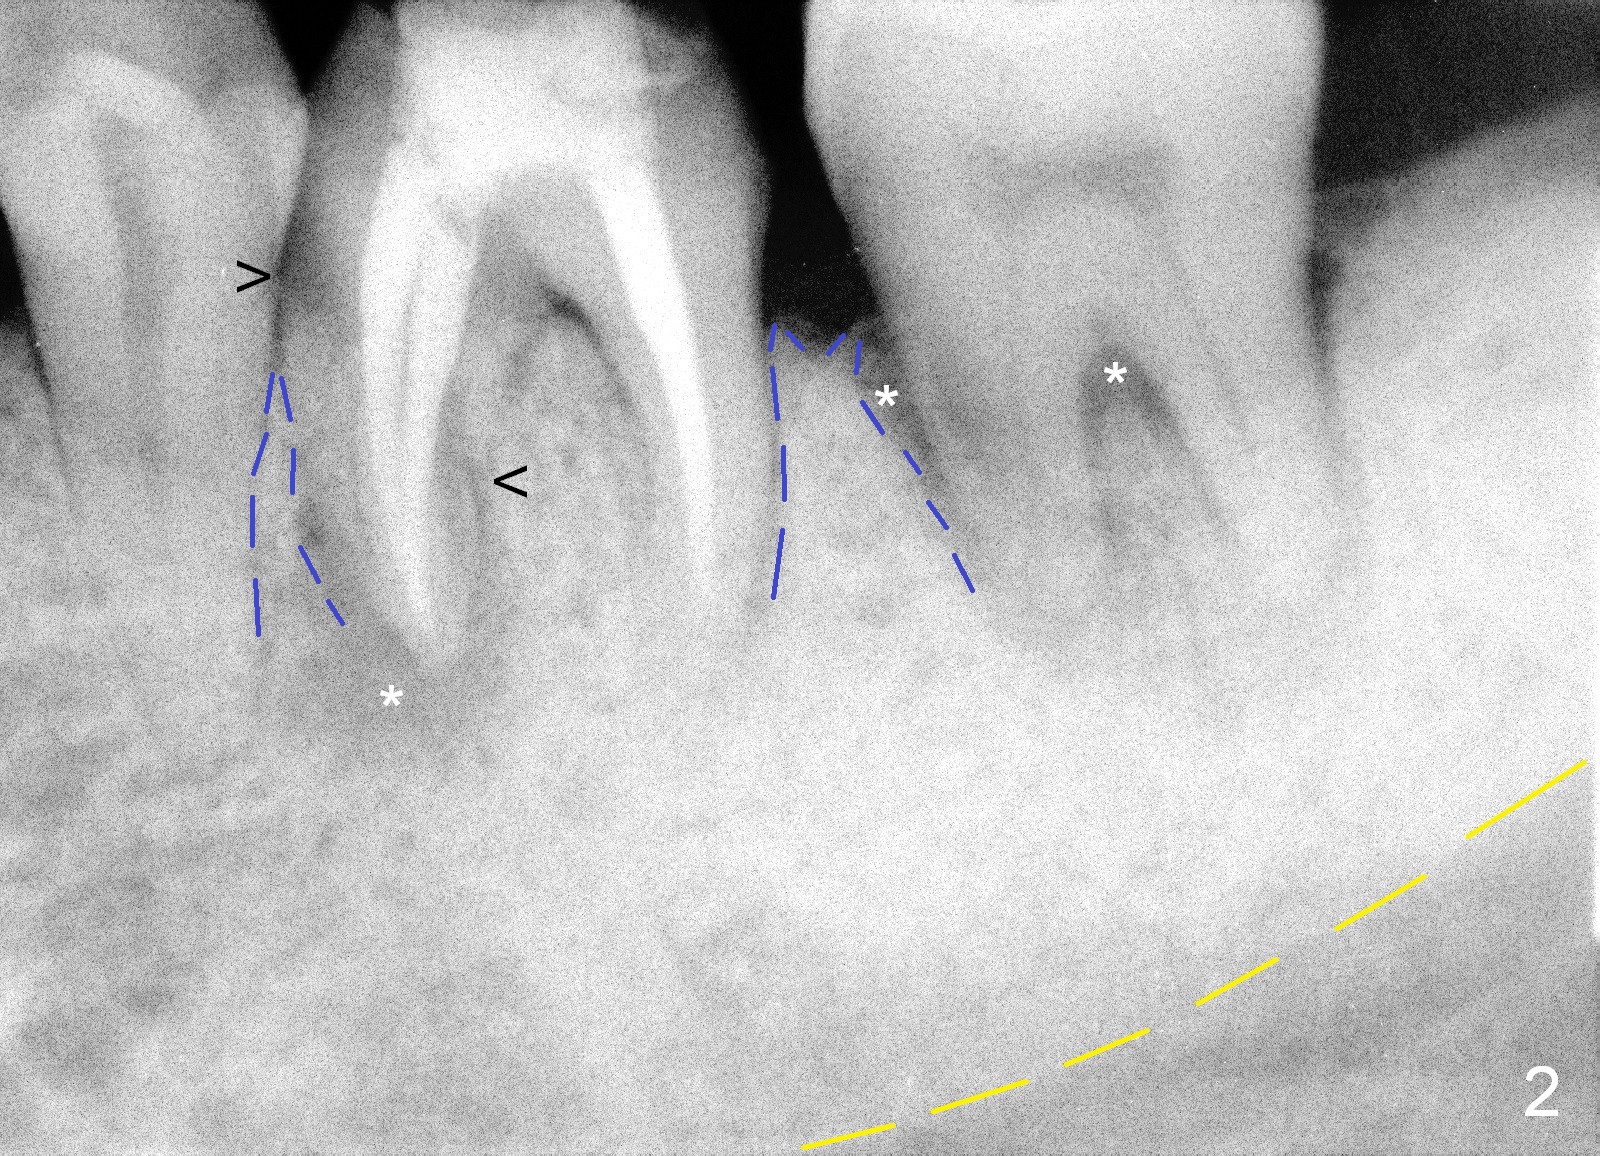

A 50-year-old man had occasional discomfort of the tooth #19 3 year ago (Fig.1). With restoration of #30 implant, the symptom disappears until now (Fig.2). He had had pain immediately before the crown of the tooth #19 was dislodged with fracture of build up. There is enlarged periapical radiolucency of the mesial root (*) with possible root fracture (arrowheads). After discussion, the patient agrees to have extraction and immediate implant.